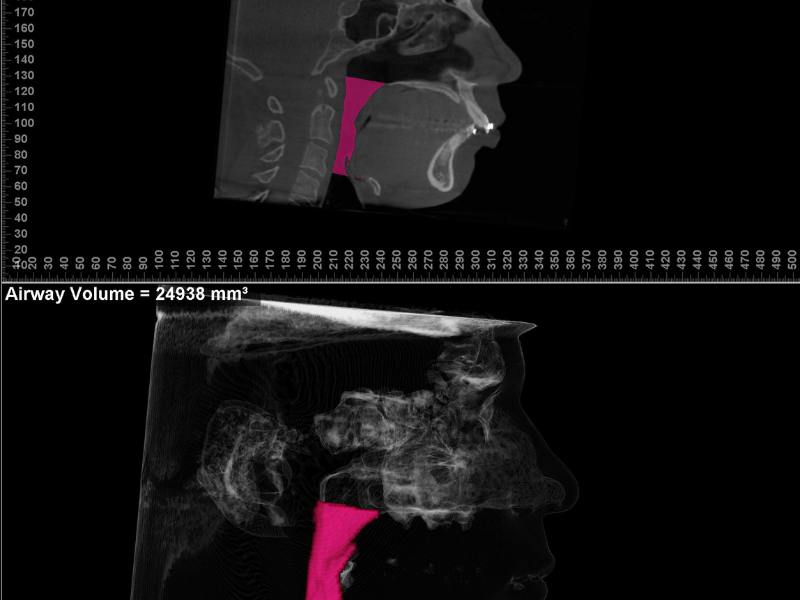

A cirurgia ortognática é um procedimento orto-cirúrgico com o intuito de restabelecer um padrão dentário e facial harmônicos, em pacientes que apresentam alterações no desenvolvimento dessa região. Destacamos uma significativa melhora nos seguintes casos: oclusão (mordida), respiração, DTM´s (disfunções temporomandibulares), harmonia da face. Cirurgia ortognática é um tratamento realizado por meio da combinação de movimentos dentários (ortodontia) e reposicionamento das estruturas dos maxilares (cirurgia). Aproximadamente 20% da população e apresentam vários graus de comprometimento estético e funcional.